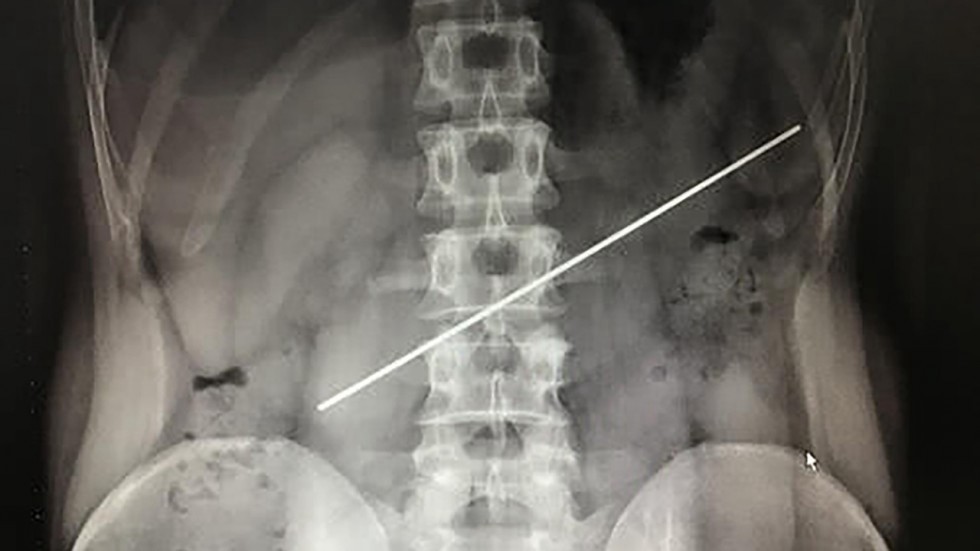

Médicos lograron extirparle una vara de acero del estómago a un hombre que la tragó como parte de una apuesta.

La cirugía de estómago se desarrolló en un hospital de la provincia de Sichuan.

De acuerdo con medios locales, el paciente había "ingerido" el objeto de 20 centímetros hace un año.

Entonces, decidió a consultar con un especialista, quien le realizó una radiografía y observó que la varilla seguía alojada en su estómago.

Además, el médico detectó que uno de los extremos del objeto había perforado la pared gástrica.